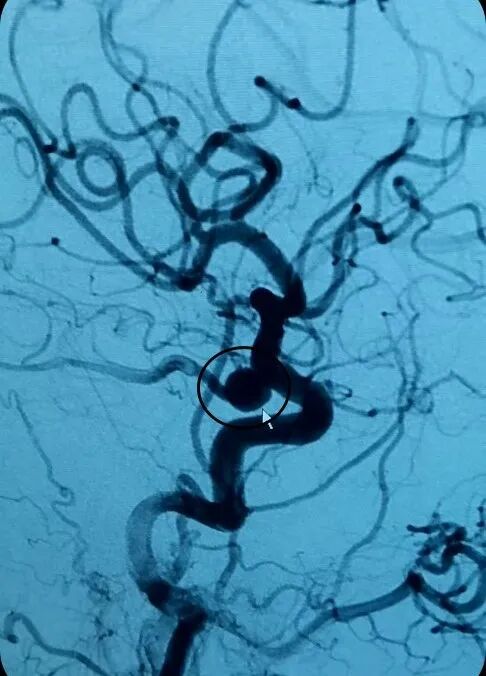

蔡冬冬醫(yī)生考慮是否顱內(nèi)有別的病灶,在征求張乃文主任的同意下,為患者行頭顱CTA(腦動(dòng)脈CT血管造影成像)檢查后,發(fā)現(xiàn)“不定時(shí)炸彈”—?jiǎng)用}瘤?;颊哂覀?cè)頸內(nèi)動(dòng)脈C7段動(dòng)脈瘤,面積約8×7mm。

因?yàn)榛颊叻磸?fù)頭痛,顱內(nèi)動(dòng)脈瘤>5mm,破裂風(fēng)險(xiǎn)較高,患者有手術(shù)指針。在報(bào)告了張乃文主任以后,張主任當(dāng)機(jī)立斷指示,立即聯(lián)系家屬,告知家屬獲益及可能出現(xiàn)的風(fēng)險(xiǎn)。家屬經(jīng)商量后決定選擇手術(shù)治療。

由神經(jīng)內(nèi)科專家張乃文主任帶領(lǐng)的醫(yī)生團(tuán)隊(duì)根據(jù)患者情況,對(duì)手術(shù)風(fēng)險(xiǎn)、并發(fā)癥及預(yù)后等進(jìn)行了全面評(píng)估,并為其制定了科學(xué)、周密的手術(shù)方案。目前動(dòng)脈瘤治療大多首選血管內(nèi)介入治療,通過(guò)血管用微導(dǎo)管向動(dòng)脈瘤內(nèi)填入彈簧圈,封堵動(dòng)脈瘤及血管破口,以起到治療作用,具有創(chuàng)傷性小、痛苦小、恢復(fù)快等優(yōu)點(diǎn)。

張乃文主任醫(yī)師團(tuán)隊(duì)與醫(yī)學(xué)影像科、麻醉科緊密配合,為患者進(jìn)行了全腦血管造影+顱內(nèi)動(dòng)脈瘤介入栓塞手術(shù),手術(shù)過(guò)程順利完成,”拆彈“成功,術(shù)后患者神志清醒,四肢肌力肌張力正常,無(wú)神經(jīng)功能缺損,恢復(fù)良好。

李阿姨手術(shù)前

李阿姨手術(shù)后